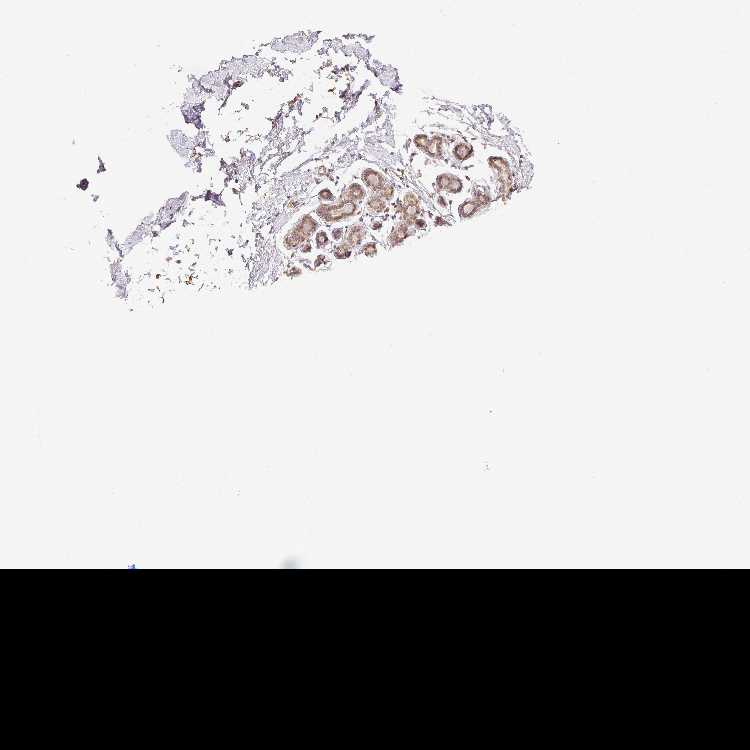

BREAST - Antibody stainingi

Antibody staining in the annotated cell types in the current human tissue is reported as not detected, low, medium, or high, based on conventional immunohistochemistry profiling in selected tissues. This score is based on the combination of the staining intensity and fraction of stained cells.

Each image is clickable and will lead to virtual microscopy that enables deeper exploration of all samples and also displays staining intensity scores, fraction scores and subcellular localization as well as patient and tissue information for each sample.

Antibody HPA044578Antibody HPA061919

Adipocytes -Not detected

Glandular cells LowLow

Myoepithelial cells LowLow